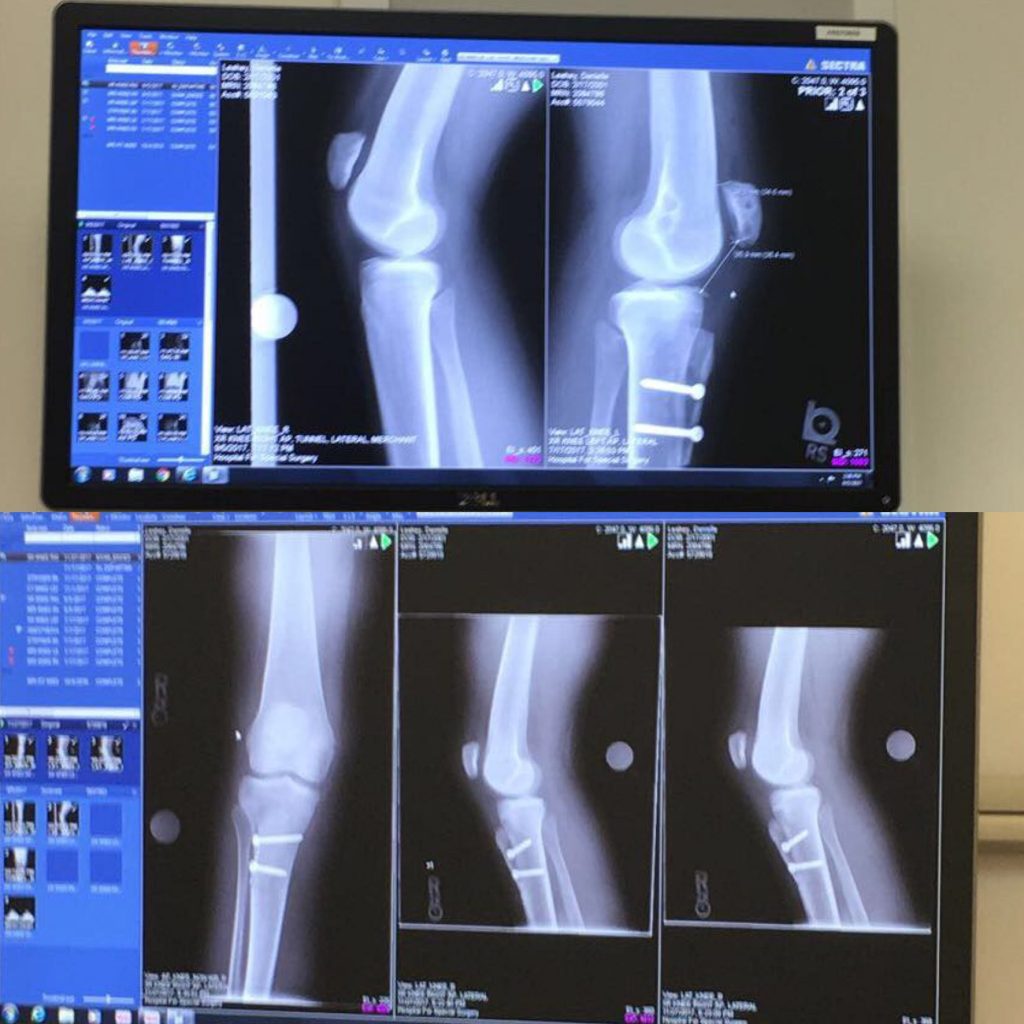

Competition was in April, I had to relearn all 5 dances. On March 20, 2015 I was at my dance studio going through our big group routine. I had to go from one side of the room to the other and I was always late. I had to speed it up my transitioning for the routine and when I did I placed my left leg and my knee popped out. Lucky when I hit the floor it popped back in. I was in pain and I was so devastated. I called my dad and he brought me home. The next day I was brought to the hospital and my mom called to make a doctor's appointment. My doctor realized something was wrong and he transferred me to the surgeon he works with. I was nervous to have a new doctor especially since he was a surgeon. The surgeon sent me to physical therapy, but this time my knee kept dislocating. My surgeon informed me that I have patella alta and trochlear dysplasia, that was the reason why it kept dislocating. We scheduled an MPFL reconstruction for December 30, 2015.

I was scared to meet Dr. Shubin Stein at first because she was my third doctor. I wanted to be done with my knee issues. When I walked in everyone was so welcoming! I was really nervous when Dr Shubin Stein came in, but she was very reassuring. She asked me to get a new MRI, and a physical therapy evaluation. The next appointment she told me I tore the graft my previous surgeon put in and said it was misplaced. My mom and I were shocked! Dr Shubin Stein then said that both my knees needed surgery and we agreed that a MPFL reconstruction and a tibial tubercle transfer was the best fit.

I had the MPFL reconstruction and TTT on my left knee on July 7, 2017. I had it done on my right on November 17, 2017. I remember both days very well! My first surgery with Dr. Shubin Stein I was scared even though I had surgery before. It was my first surgery with her and I only had two-three appointments before then. Dr. Shubin Stein could tell I was nervous because she tried to take my mind off of it. She said that I could have personally asked her if I would be back to tennis in time instead of asking over the HSS Facebook Live she participated in. It made me laugh and smile. Both times Dr. Shubin Stein made me feel relaxed and confident about surgery.